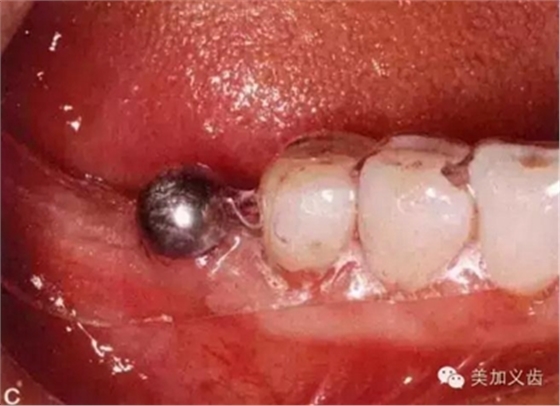

拍片時(shí)怎么把小剛球固定在口內(nèi)?有的牙醫(yī)用紅蠟把它固定在鄰牙上,這是一種比較玩火的做法,一旦掉了怎么辦?重新拍?一旦患者把小剛球咽到肚子了怎么辦?讓患者賠你小鋼球?我一定是在開玩笑,呵呵,患者不讓你賠錢就不錯(cuò)了。

別嫌麻煩,給患者術(shù)前取個(gè)模型,然后通過(guò)壓膜來(lái)制作放射導(dǎo)板,這樣小剛球就固定在導(dǎo)板里了,別說(shuō)你的診所沒(méi)有壓膜機(jī)哈......

然后將導(dǎo)板放到口內(nèi)進(jìn)行拍攝就可以了。